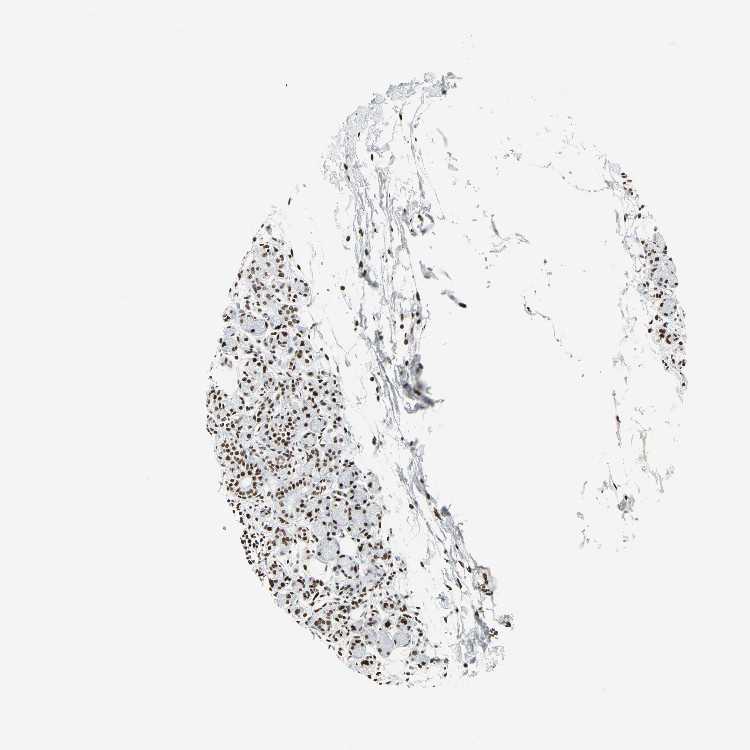

ADIPOSE TISSUE - Antibody stainingi

Antibody staining in the annotated cell types in the current human tissue is reported as not detected, low, medium, or high, based on conventional immunohistochemistry profiling in selected tissues. This score is based on the combination of the staining intensity and fraction of stained cells.

Each image is clickable and will lead to virtual microscopy that enables deeper exploration of all samples and also displays staining intensity scores, fraction scores and subcellular localization as well as patient and tissue information for each sample.

Antibody HPA011727Antibody CAB005054

Adipocytes HighHigh